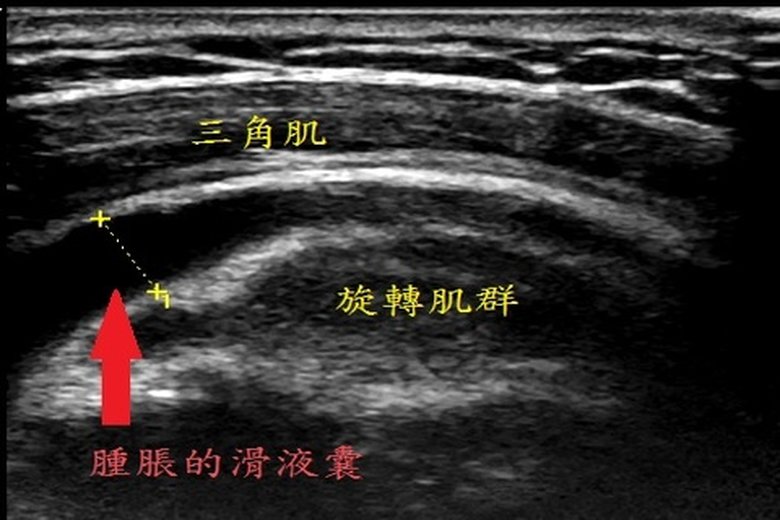

復健科主任羅嘉元說明三角肌下滑液囊腫脹變大的原因。(朴子醫院提供)

羅嘉元進一步表示,三角肌下滑液囊位於肩部三角肌與旋轉肌群之間,此滑液囊發炎常造成肩關節「夾擠症候群」。常見症狀包括:手臂往外側或前側高舉至某個角度會造成疼痛,但繼續往上抬仍然可以舉到耳朵旁邊;睡覺時無法往患側躺。常發生三角肌下滑液囊炎的族群有:需要反覆把手抬高過肩的運動選手(游泳、網球、排球、羽球)、搬運工、家庭主婦等。

嘉元指出,治療三角肌下滑液囊炎的方法包括:避免反覆手臂高舉過肩的動作;口服非類固醇消炎止痛藥緩解發炎和腫脹所帶來的疼痛;物理治療方面可以使用儀器治療,例如:紅外線、雷射及經皮電刺激緩解疼痛。如果上述方法無效時,可以安排肩部肌肉骨骼超音波檢查,在超音波底下可以看到三角肌下滑液囊腫脹變大,進行滑液囊積液抽吸並施行注射治療。